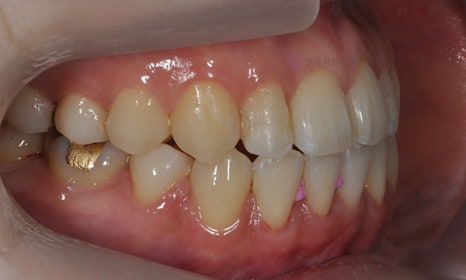

다음 케이스 역시 위 아래 중심선의 차이가 있어서 비대칭이 있어 보이는 케이스입니다. 중심선의 차이 뿐 아니라 앞니 및 어금니 부위에 거꾸로 물리는 반대교합이 관찰되고 있었습니다(원래는 위 치아가 아래 치아를 덮는 것이 정상적인 교합이나, 반대교합이란 위 치아가 아래 치아보다 더 안쪽으로 들어가서 물리는 교합을 말합니다).

2020.2

얼굴의 중심선과 위 치아의 중심선은 일치하여, 오른쪽 아래 작은 어금니를 발치하여 그 공간으로 아래 치열을 이동시켜줌으로써 중심선 및 교합을 개선하였습니다.